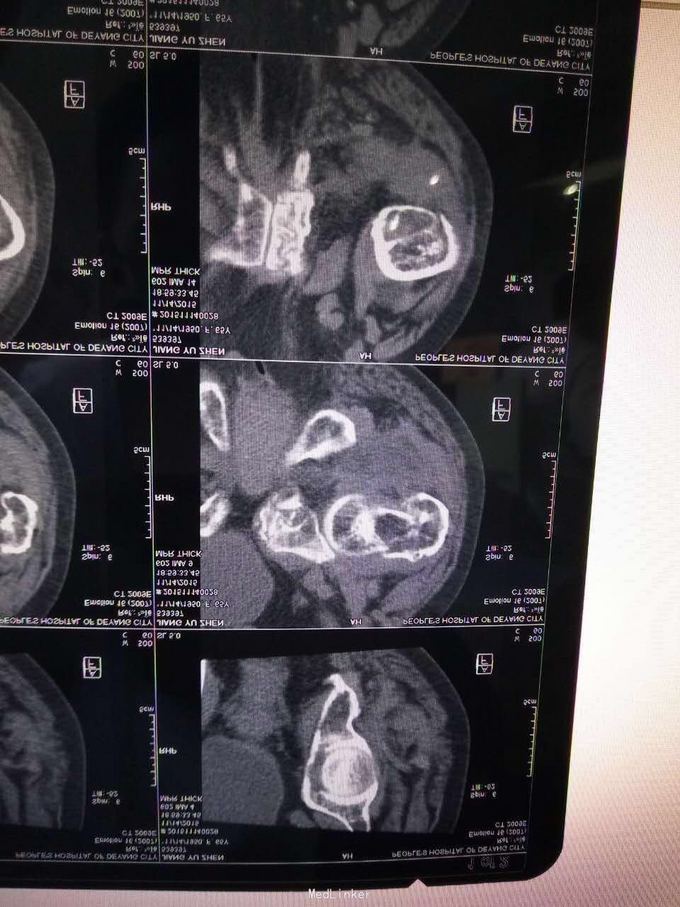

查体,左下肢外旋畸形,髋部压痛,轴向叩击痛。 x片提示:左股骨颈、转子间骨折,左股骨耻骨上支,耻骨联合、下肢粉碎性骨折。

诊断:左股骨颈、转子间粉碎性骨折,左耻骨上支、耻骨联合、下支粉碎性骨折,重度骨质疏松症, 处理:患肢制动,牵引,注射鲑降钙素,科室讨论意见为行髋关节置换术,与换方沟通后,换方表示拒绝手术治疗,主动出院。